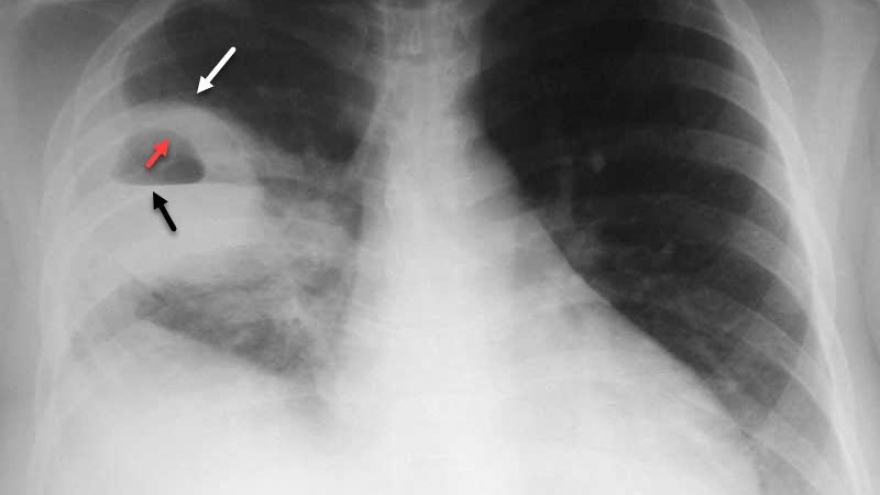

VOV.VN - Bệnh viện Đa khoa tỉnh Sóc Trăng cho biết, cùng với sự nỗ lực nâng cao chuyên môn và hỗ trợ từ Bệnh viện Đa khoa Trung ương Cần Thơ, vừa qua, Khoa Ngoại Tổng hợp Bệnh viện Đa khoa tỉnh Sóc Trăng đã điều trị thành công cho bệnh nhân bị áp xe phổi nhờ triển khai kỹ thuật mới.